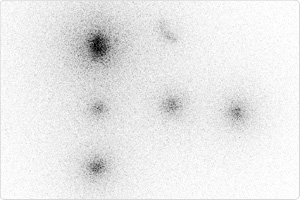

オートラジオグラフィー(英: autoradiography)は、放射線写真法やオートラジオグラムとも呼ばれ、分布している放射性物質から放出されるベータ線粒子やガンマ線から画像(オートラジオグラフ)を作成する手法である。生物学においては、放射性物質が特定の組織に滞留することを確認する手法として用いられる。放射性物質は、代謝系経路に導入されたり、レセプターや酵素に結合したり、核酸に組み込まれたりする。オートラジオグラフの撮影のために、放射性アイソトープでラベルされた組織部にフィルムや乾板をあてる。

組織内にレセプターがどのように分布しているかを特定するため、放射性アイソトープでラベルされたリガンドが用いられる。in vivoの場合には、組織を切除したり区分けするなどの前処置をした後、リガンドを循環系に導入する。in vitroの場合は、組織片にリガンドを添加する。リガンドは、一般的に3H(トリチウム)や125Iが用いられる。放射性ラベルされたオリゴヌクレオチドやRNA("riboprobes")を用いて組織内でのRNA翻訳の分布を調べる手法は、in situ hybridization histochemistryと呼ばれる。RNAやDNAウイルスの配列もこの手法で検知できる。これらのプローブは、32P、33P、35Sで通常ラベルされる。